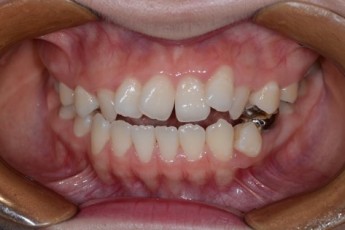

BEFORE & AFTER

- 덧니교정